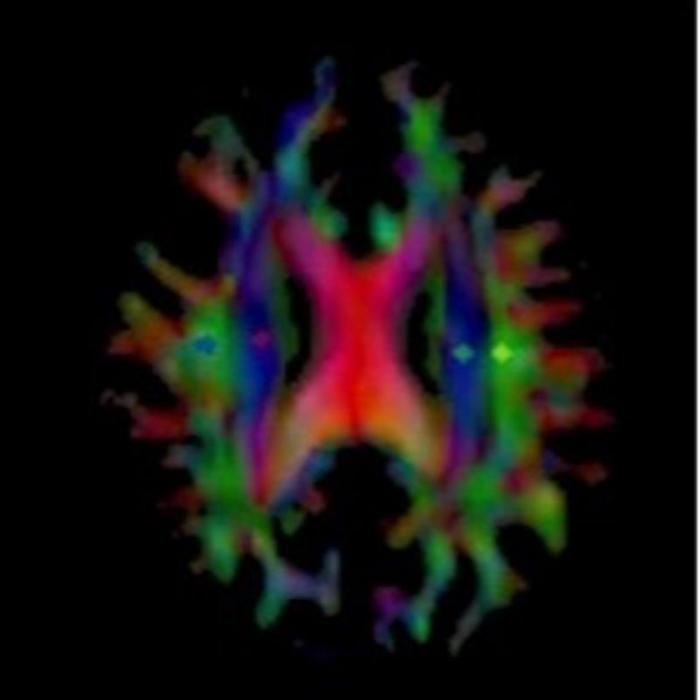

Map of an Alzheimer's patient's brain showing the diffusion of water as part of glymphatic flow (IMAGE)

MRI scans were performed before and after the initiation of treatment for Alzheimer's disease patients, and the DTI-ALPS index was calculated. Colors show regions of interest in the brain